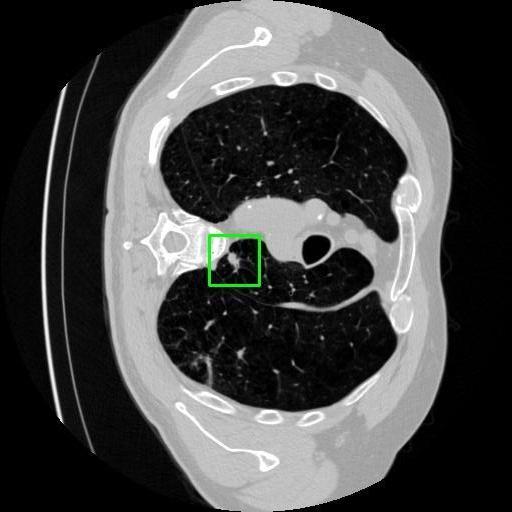

We developed an AI-based system using deep learning models for analyzing lung CT scans to detect and classify pulmonary nodules. We chose the YOLOv11 architecture for its enhanced object detection capability and adapted it specifically for medical imaging, incorporating pixel-level precision and severity classification.

Classification into three severity levels with colored bounding boxes.

Designed a severity classification system that categorizes nodules into null, moderate, and severe using colored bounding boxes, assisting in rapid clinical decision-making.